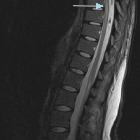

Systemic air

embolism and decompression illnes in a scuba diver.. MR imaging on sagittal view in T2WI with fat signal saturation. Arrow shows a linear area of hyperintensity involving the spinal cord at T8-T9 level, indicative of hypoxic suffering.

embolism and decompression illnes in a scuba diver.. The previous MR imaging finding (T2WI), on axial view.